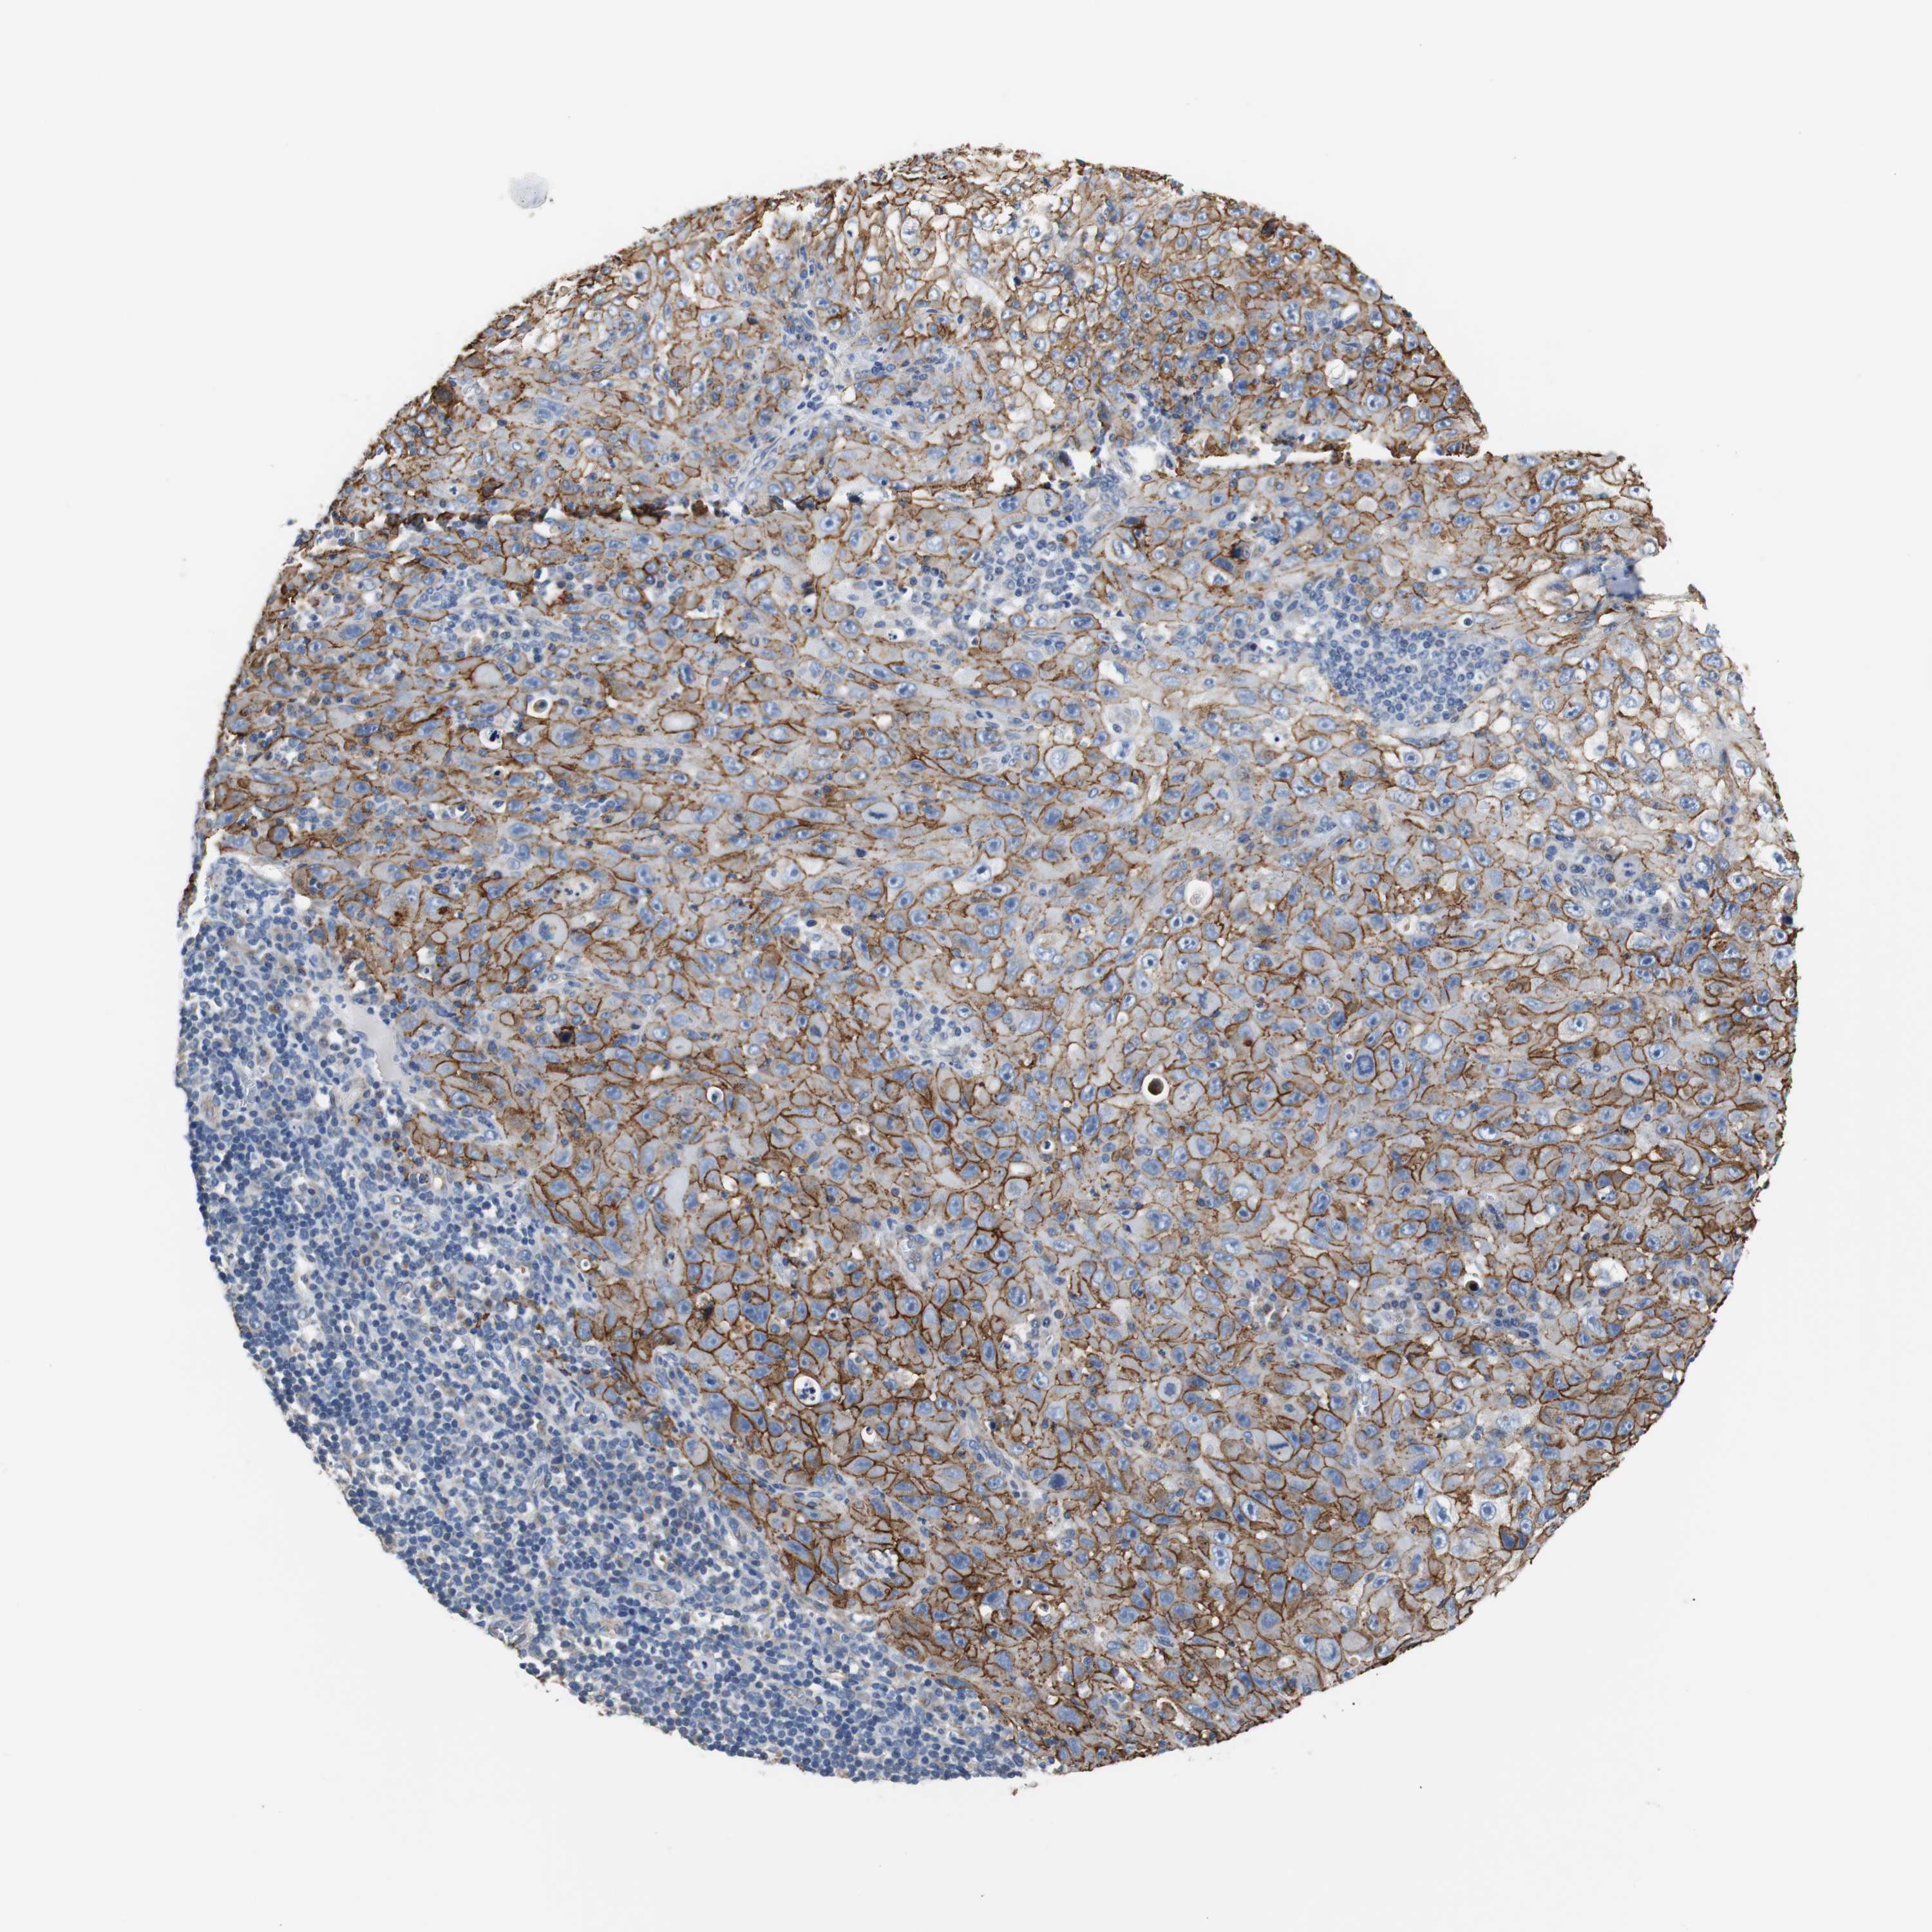

SKIN CANCER - Protein expressioni

A mouse-over function shows sample information and annotation data. Click on an image to view it in a full screen mode. Samples can be filtered based on level of antibody staining by selecting one or several of the following categories: high, medium, low and not detected. The assay and annotation is described here.

Each image is clickable and will lead to virtual microscopy that enables deeper exploration of all samples and also displays staining intensity scores, fraction scores and subcellular localization as well as patient and tissue information for each sample.

Antibody HPA006277

Antibody HPA006507

Antibody CAB017027

Staining

High

Medium

Low

Not detected

Intensity

Strong

Moderate

Weak

Negative

Quantity

>75%

75%-25%

<25%

None

Location

Nuclear

Cytoplasmic/membranous

Cytoplasmic/membranous,nuclear

Squamous cell carcinoma, NOS